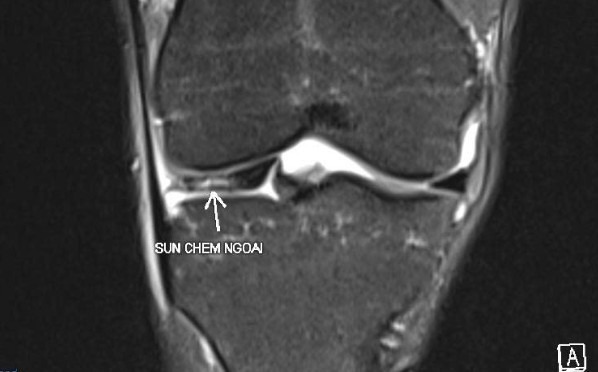

Ngoài ra cũng xuất hiện thêm những ca chấn thương liên quan đến đứt dây chằng, đứt gân gót khi chơi pickleball dù trước đó chưa từng gặp phải chấn thương tương tự khi chơi Tennis hay cầu lông. Bên cạnh đó, cũng ghi nhận trường hợp người chơi pickleball bị đau khớp sau 3 tiếng chơi liên tiếp. Kết quả chụp MRI cho kết quả rách sụn chêm dạng phức tạp, mảnh sụn di chuyển vào trong khớp gây 'kẹt gối'. Thậm chí, còn nghi nhận thêm một phụ nữ 44 tuổi chơi pickleball tới 5 tiếng mỗi ngày khiến khớp gối bị thoái hóa nghiêm trọng và có thể dẫn tới tàn phế.